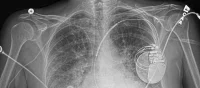

Alsace e-santé, the coordinator for a grouped procurement for the SIMRAL project, will deploy an innovative solution for sharing medical images across the region for 53 healthcare enterprises , along with consolidated functions for VNA (vendor-neutral archiving), image management with PACS (picture archiving and communication system) and RIS (radiology information system), together with Agfa HealthCare and Worldline.

SIMRAL is a major project for Agfa HealthCare, and the first regional project in France with such a large scope, covering pooled, hosted services for PACS, RIS, VNA and image sharing for healthcare professionals. "Secure, immediate and direct access to medical images will allow physicians to improve their follow-up of patients, especially in cases involving cancers or chronic illnesses," explains Dr. Pascal Charles, Manager of Alsace e-santé and independent pulmonologist. "SIMRAL will also make it possible to eliminate unnecessary examinations and to thus decrease the risks associated with cumulative radiation dose and use of contrast agents."